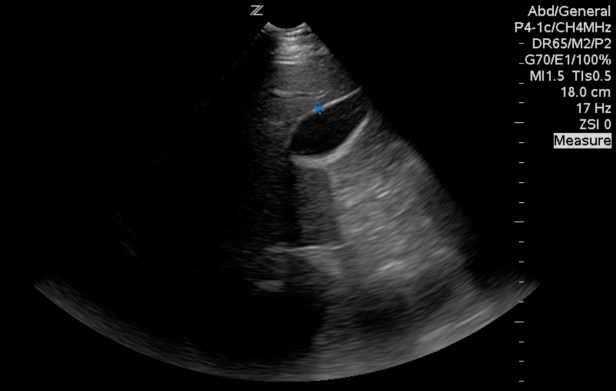

Right way: